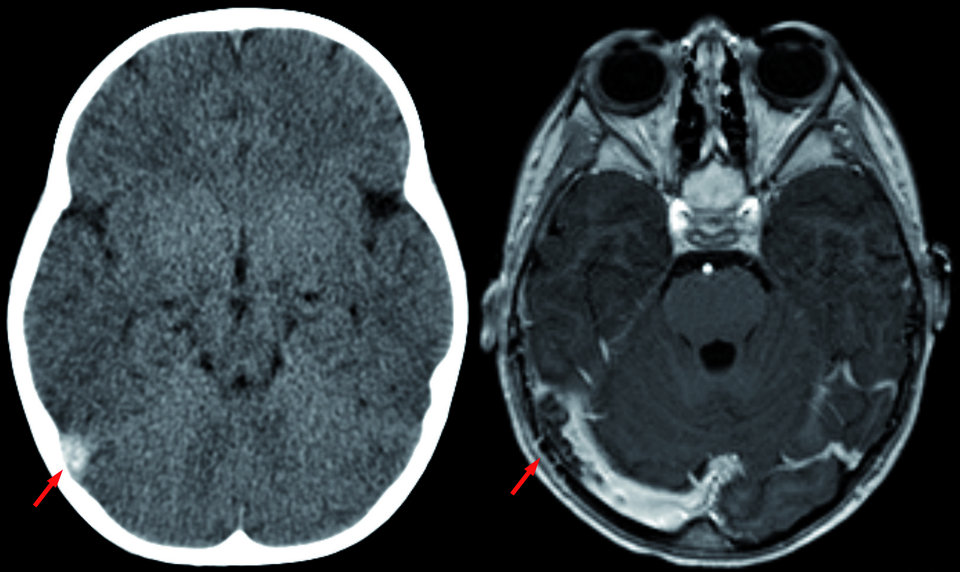

• Medikamente (z.B. Chemotherapie)

Im CT ohne Kontrastmittel (links) und im MRT mit Kontrastmittel (rechts) lässt sich eine Sinusvenenthrombose gut erkennen. Im CT ohne Kontrastmittel (links) und im MRT mit Kontrastmittel (rechts) lässt sich eine Sinusvenenthrombose gut erkennen. © wikimedia/Hellerhoff